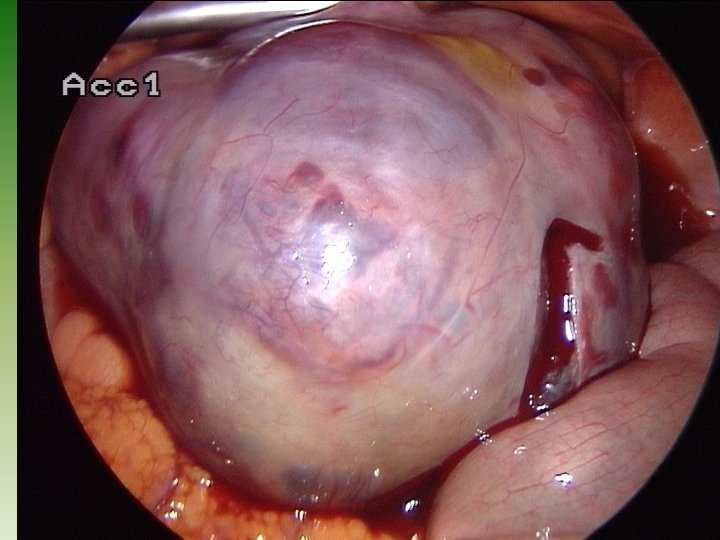

Wie viele präantrale Follikel müssen koaguliert werden ? ? ? Abhängig vom AMH: etwa 50 % der präantralen Follikel bei Werten von > 7, bis zu 70 % der präantralen Follikel bei Werten über 15 Wichtig: nur vorübergehender Effekt, Wirkung hält ca. 2 Jahre an, bei niedrigeren Werten, ev. Clomiphen oder Gonadotropin, niedrig dosiert bei hohen Werten: eher IVF, ev. mit Einfrieren aller Embryonen

AMH: vor Operationen Einschätzung zum operativen Vorgehen Wert unter 1, 0 ng/ml: Vorsicht vor jeder weiteren Zerstörung von Ovarialgewebe: insbesondere bei Cysten- und Endometriosefällen Werte über 10, 0 ng/ml relativ viele präantrale Follikel müssen einem drill & dott unterzogen werden jedoch: auch Gefahr der Übertherapie nach Operationen: Wert der vorangegangenen Operation kann eingeschätzt werden